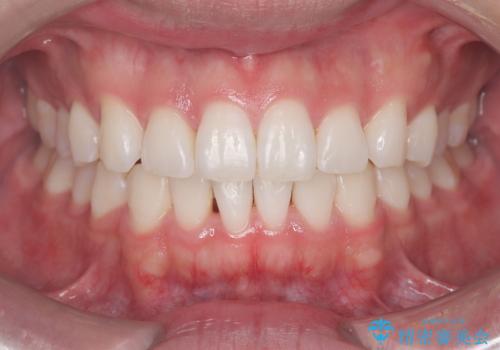

[マウスピース矯正] がたがたの歯並びをきれいにしたい

![[マウスピース矯正] がたがたの歯並びをきれいにしたいの症例 治療前](https://seimitsushinbi.jp/wp/wp-content/uploads/2025/06/0d238550c8a0fddc4de7b2c337c6c786-500x350.jpg?v=1750323380)

![[マウスピース矯正] がたがたの歯並びをきれいにしたいの症例 治療後](https://seimitsushinbi.jp/wp/wp-content/uploads/2025/06/IMG_0002-2-500x350.jpg?v=1750323305)